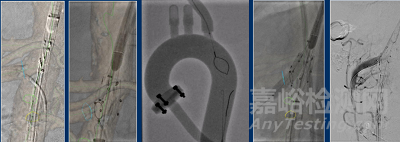

WeFlow-JAAA腹主動脈覆膜支架系統(tǒng)設計目的主要是治療近腎腹主動脈瘤。其結構包括1個開槽、1個窗孔和2個內嵌分支分別用以CA、SMA、和RA的重建。開槽和開窗邊緣有密封環(huán)設計用于防止內漏。該產品無需定制,可規(guī)格化生產。輸送系統(tǒng)預置了3根導絲以快速建立分支動脈軌道。使用時主體經股動脈入路,到達預定位置半釋放,由鎖骨下動脈入路抓出預置導絲,重建SMA、CA和雙側RA,最后重建髂動脈。

輸送系統(tǒng)預置3根導絲,以快速建立分支動脈軌道。使用時,主體經股動脈入路,到達預定位置半釋放,由鎖骨下動脈入路抓出預置導絲,重建CA和雙側腎動脈,最后重建髂動脈。

預埋導絲可在DSA下清晰顯示

WeFlow-JAAA通過保留CA、單開窗重建SMA、內嵌分支重建雙RA,為JAAA和部分腎旁AAA的腔內治療提供了全新的解決方案。